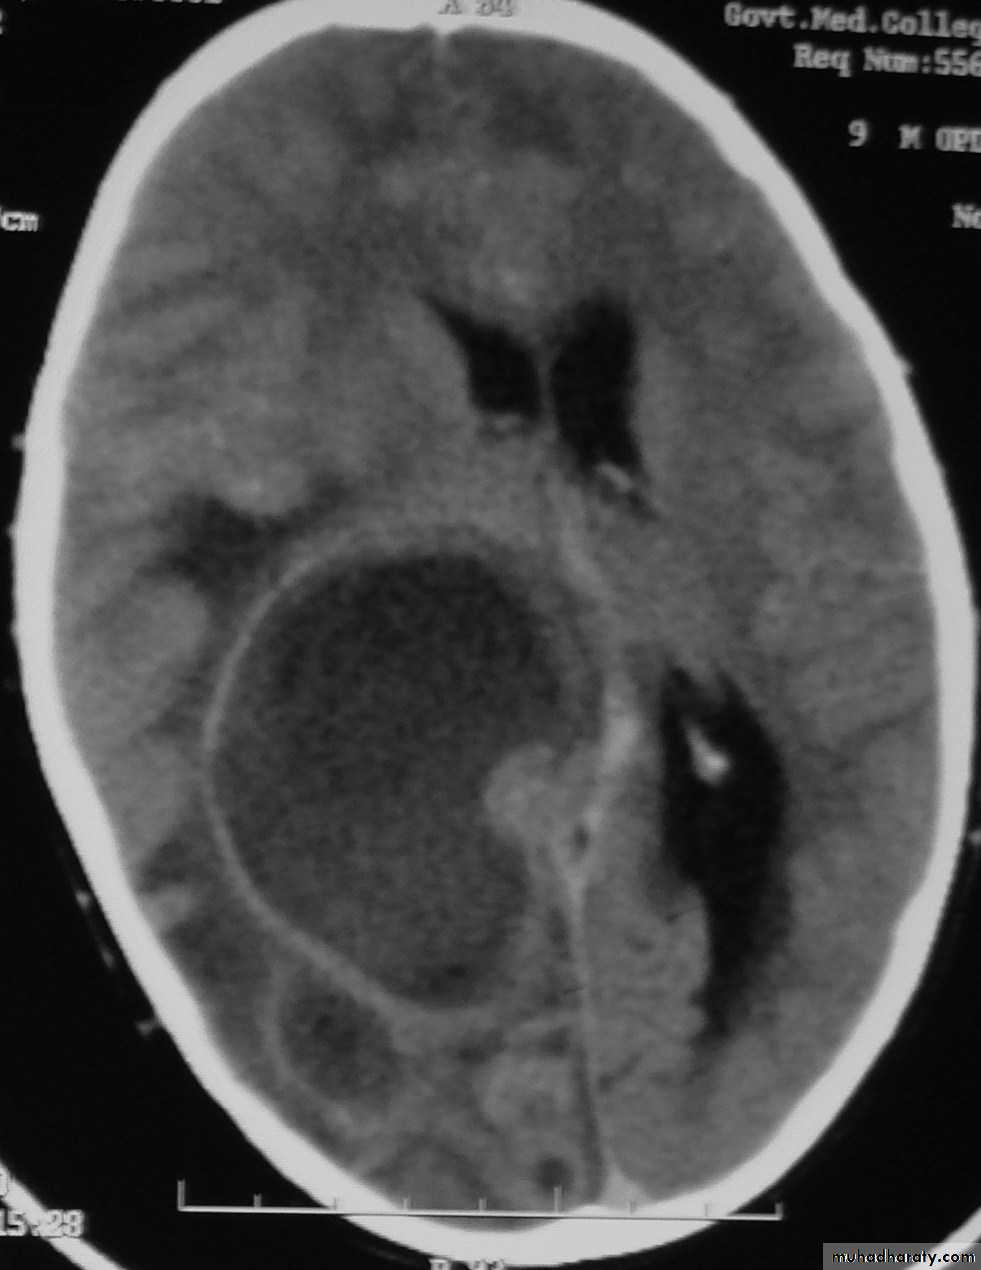

• B. Radiological Investigations:• CT or MRI is the investigation of choice.

• CT Brain is performed with and without contrast.

• MRI is done with gadolinium enhancement.

• They will show a single (or multiple) space occupying lesion that is well delineated with an enhancing wall, with variable surrounding oedema.

Brain Abscess CT without contrast

Brain Abscess CT with contrast

• B. Radiological Investigations:• The differential diagnosis of a single brain abscess in CT or MRI is a solitary metastasis or cerebral infarction.

• The differential diagnosis of multiple brain abscesses is from multiple metastasis and tuberculoma.